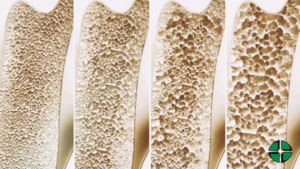

L’osteoporosi è una patologia sistemica, una malattia metabolica del tessuto scheletrico, caratterizzata dalla progressiva e graduale riduzione della massa ossea. Le ossa cominciano a perdere volume perché minerali come sali di calcio, magnesio, fosfati, cominciano a distaccarsi.

Le ossa hanno una densità inferiore e la loro microarchittetura si deteriora. Un osso con meno minerali quindi, si presenta più poroso, e un osso più poroso diventa più fragile, più debole e a risentirne sarà l’intero apparato scheletrico che vedrà diminuita la sua resistenza meccanica e risulterà essere maggiormente predisposto a subire fratture.